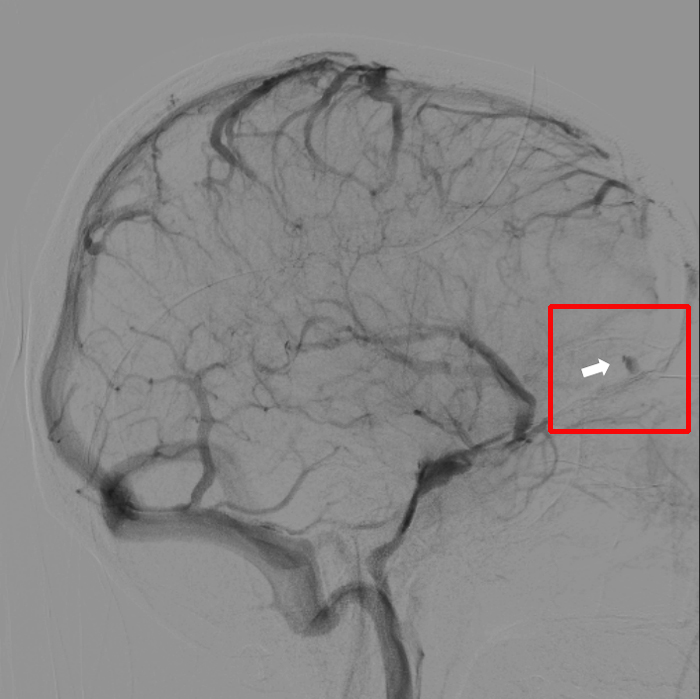

3个月过去了,小董再次来到潞河医院神经外科,由张洪兵主任牵头,组织多学科评估、讨论,认为小董的病情复杂,非常适合复合手术室进行手术,经过详细的术前讨论及术前准备,手术按计划顺利进行。首先进行脑血管造影,术中明确了硬脑膜动静脉瘘残留位置。随后张洪兵主任带领团队成员应用显微技术成功切除了残余的血管畸形,术中造影证实切除完全,同期成功钛网修补颅骨。经过两次完美的治疗,小董顺利出院。现在小董恢复很好,已回归社会,开始正常的工作生活。

复合手术前